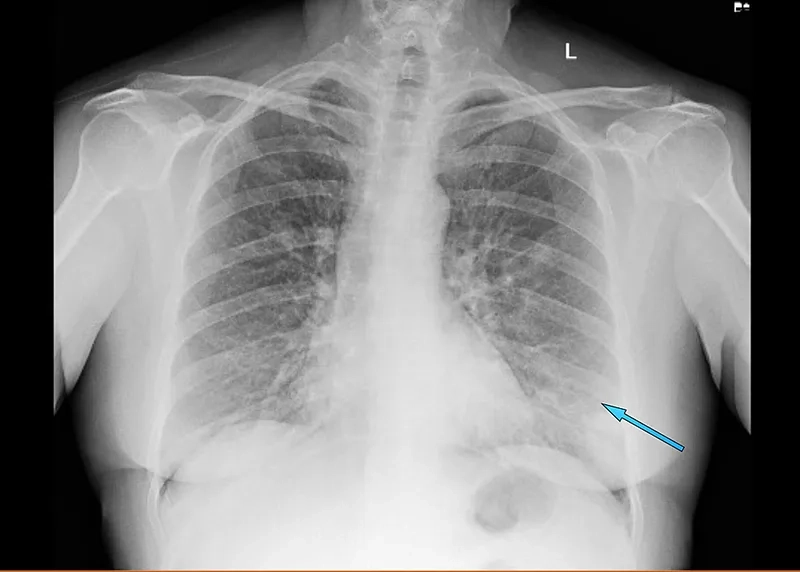

Image of the disease Rhinovirus Infection